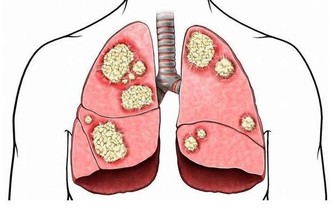

中醫認為,肺與秋季相應,而秋季乾燥,氣燥傷肺,肺氣虛則機體對不良刺激的耐受性下降,易產生疾病,因為需要潤燥、養陰、潤肺。

中醫學認為,苦燥之品易傷津耗氣。秋季燥邪當令,肺為嬌臟,與秋季燥氣相通,輕易感受秋燥之邪。許多慢性呼吸系統疾病往往從秋季開始復發或逐漸加重。所以,秋令飲食養生應忌過燥的食物,比如一些煎炸類的食物。